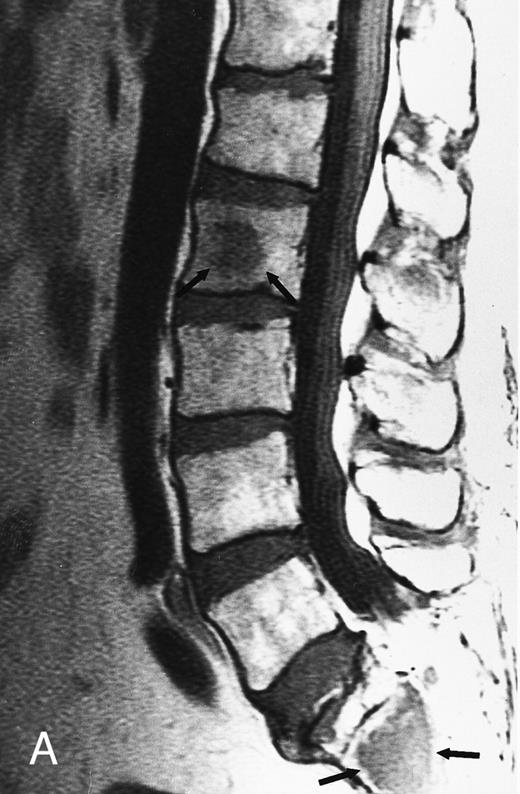

Focal MR pattern of abnormal marrow in a 48-year-old man with multiple myeloma: T1-weighted (500/10, TR/TE) (A), T2-weighted, fat-suppressed fast spin echo (5000/96, TR/TE, ET 16) (B), and enhanced T1-weighted (500/10, TR/TE) (C) sagittal MR images of the lumbar spine. Focal lesions (arrows) in L2 and S1 are dark in (A), bright in (B), and in (C) they enhance and become almost imperceptible from the uninvolved marrow.